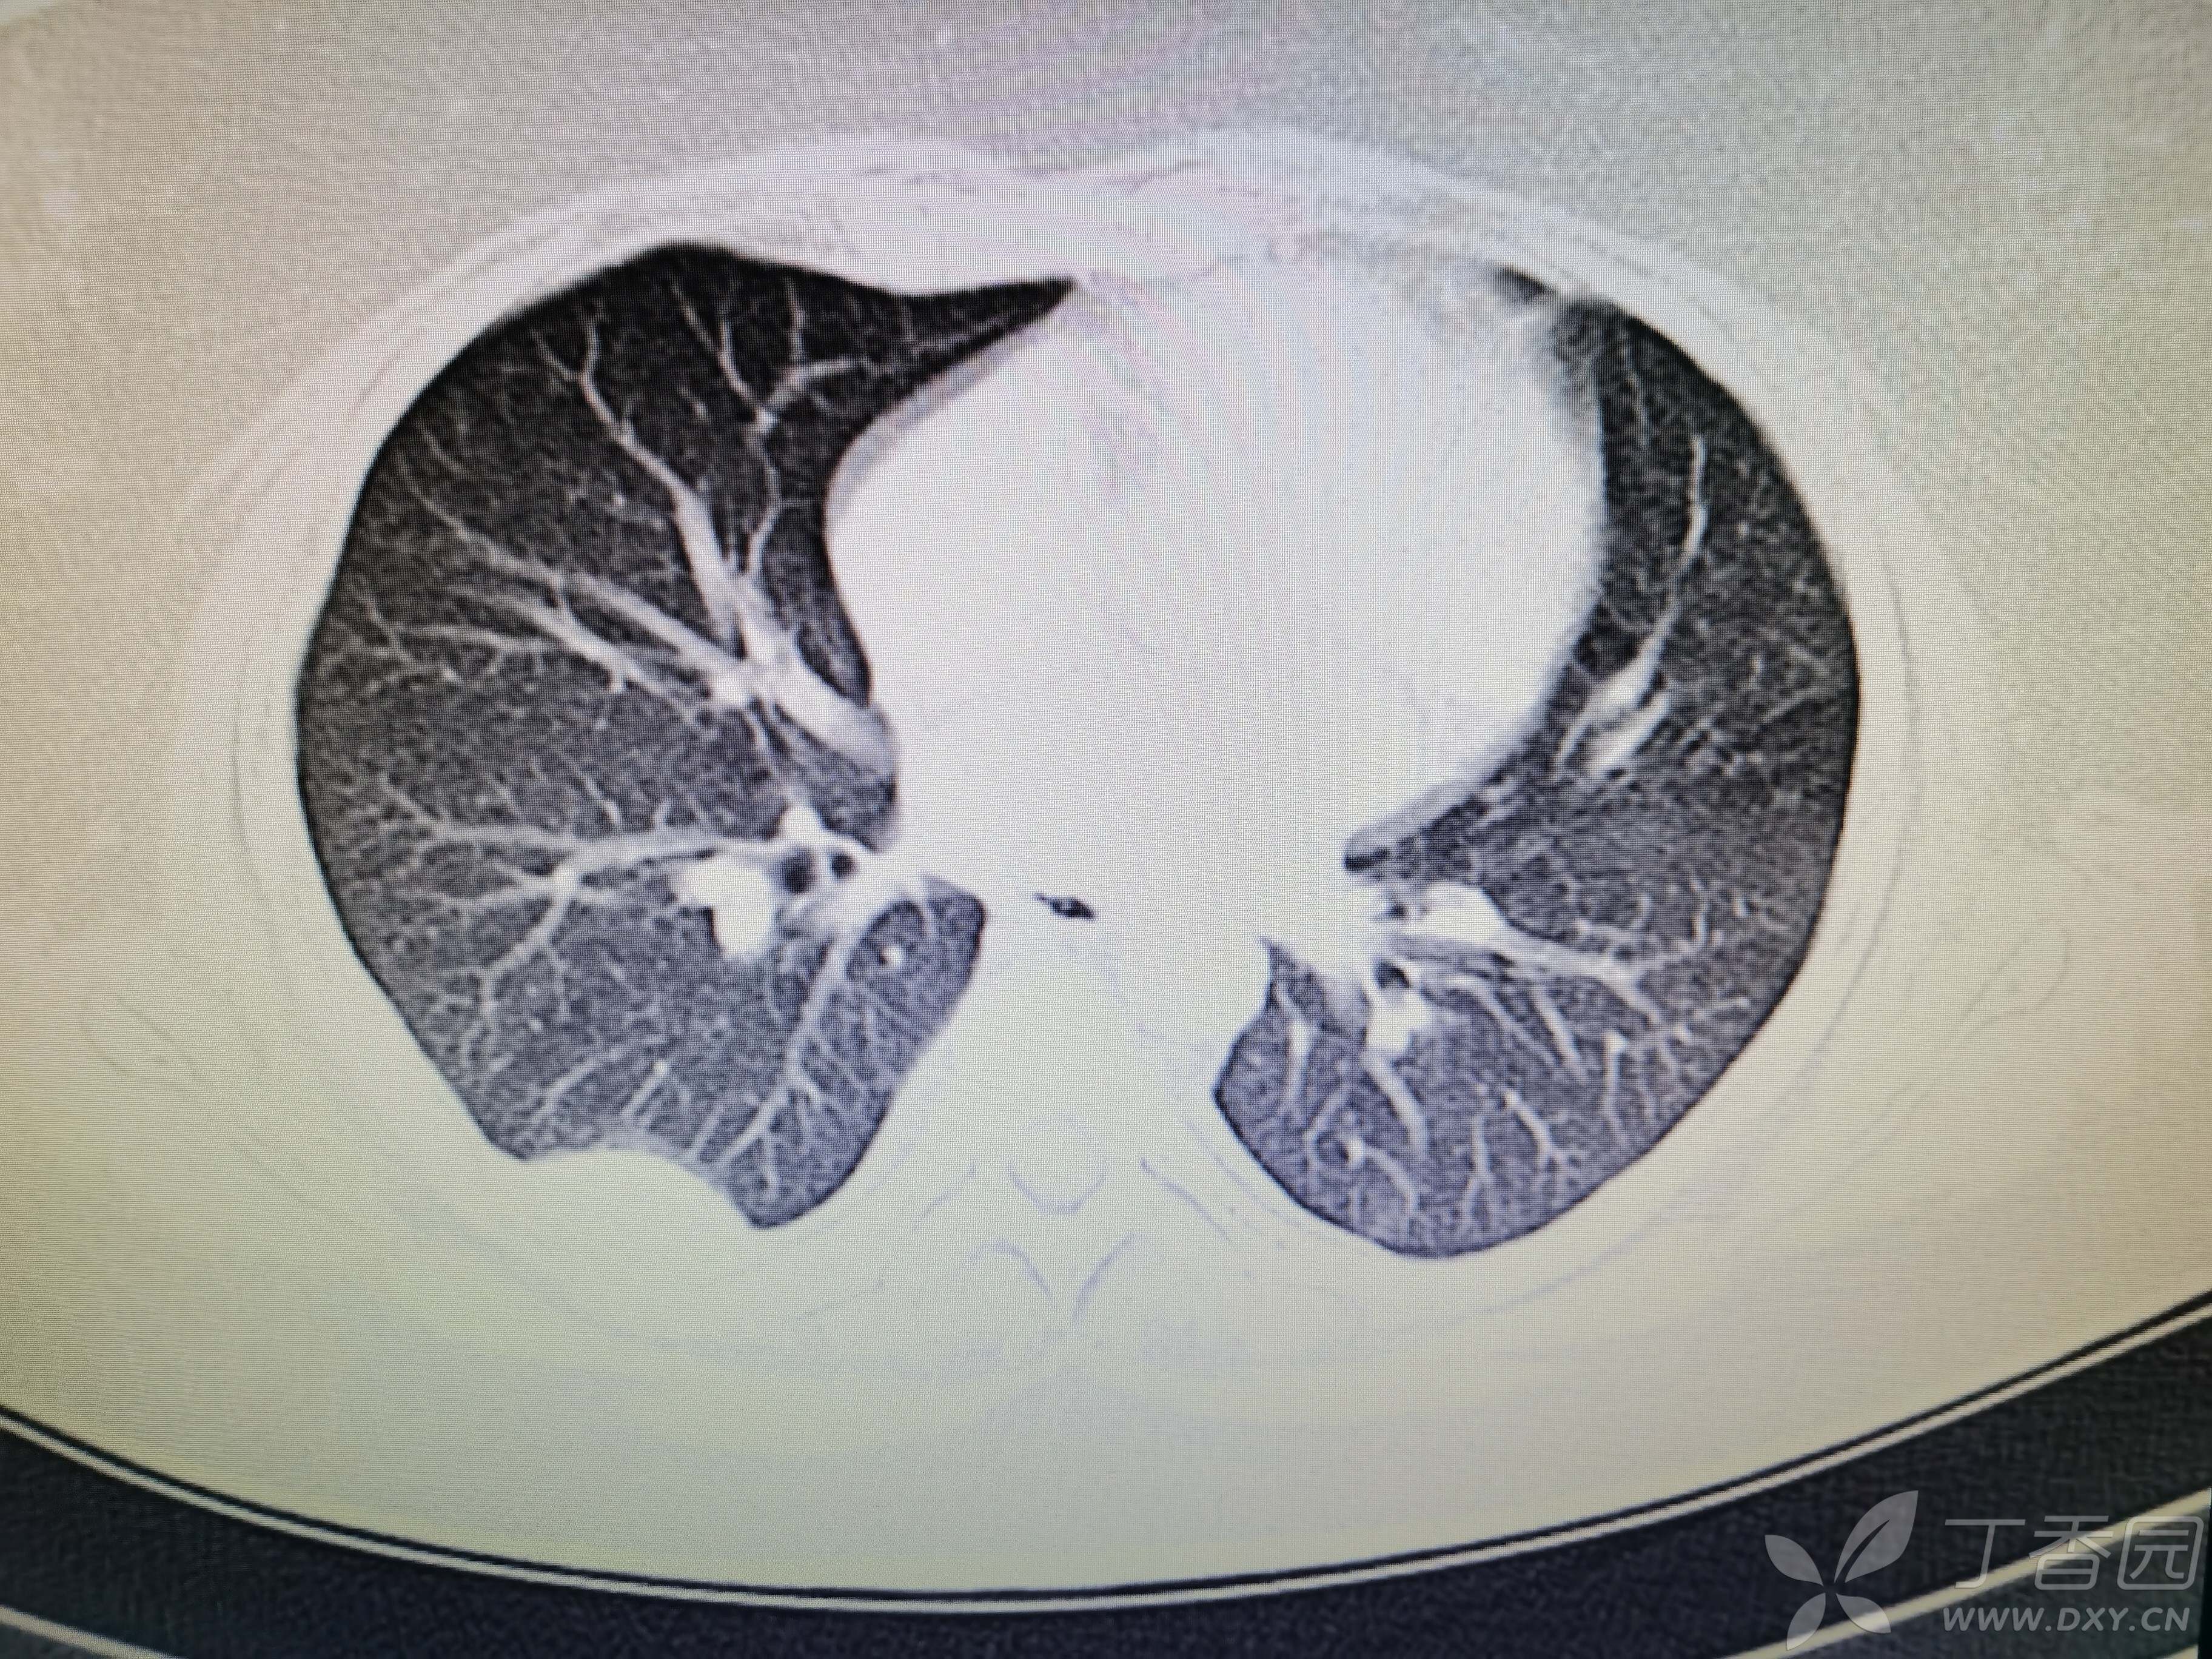

基本信息:女,三十几岁,印度人。。

胸部CT:

如题:猜肺部病灶病理。。